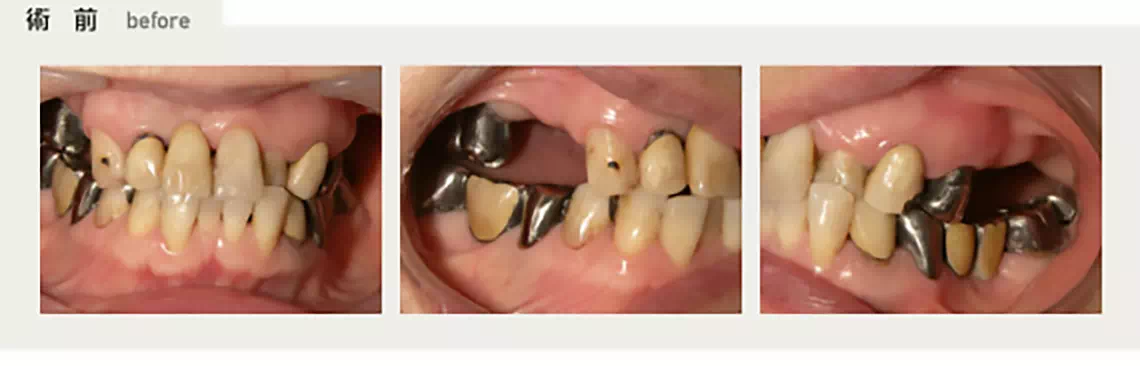

部分的に歯が無い方 60代 男性

右下に着脱式の入れ歯を入れていましたが、異物感が強く美味しく食事が出来ないとのことで3本のインプラント治療を作ることになりました。